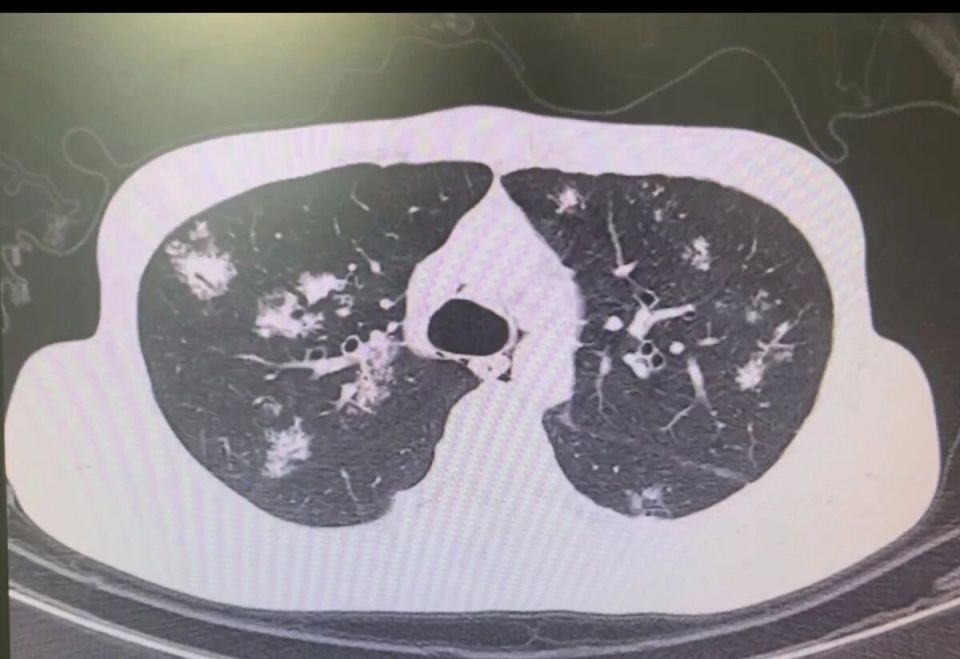

当遇到多发的肺部结节时,这就好比孙悟空进了一个满是妖怪的山洞,每个妖怪都可能有不同的“法力”(危害程度),得仔细辨别,谨慎应对。

但更多时候,结节就像分散在不同山头的妖怪,左肺、右肺都有。

这时候,医生就得像孙悟空一样,火眼金睛地找出那个最厉害、最可能带来危害(转移等)的主病灶,优先把它解决掉。